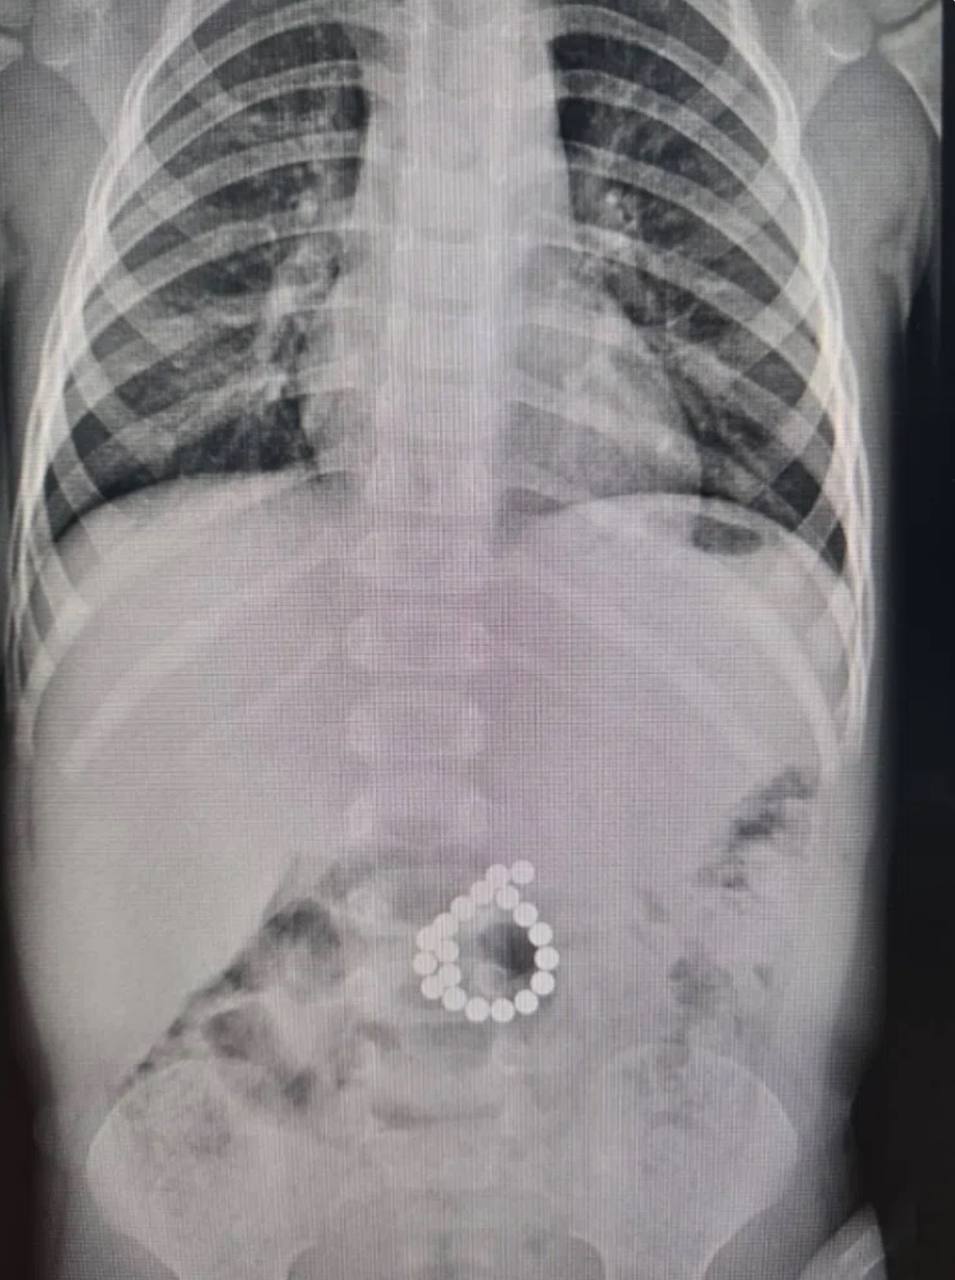

Двухлетний ребенок из ХМАО проглотил магнитный конструктор и попал в больницу с высокой температурой, сильными болями в животе. В его желудке было обнаружено 19 шариков оказалось внутри

Ребенку провели операцию. После этого он провел шесть суток реанимации. Сейчас ребёнок в хирургическом отделении, состояние стабильное